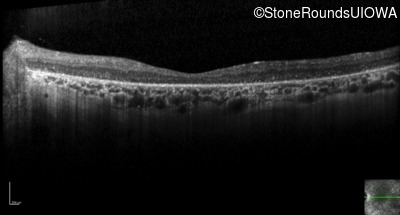

Optical Coherence Tomography - Right - 10/140 sc

Exemplar / OCT Stack

Optical Coherence Tomography - Left - 10/180 sc